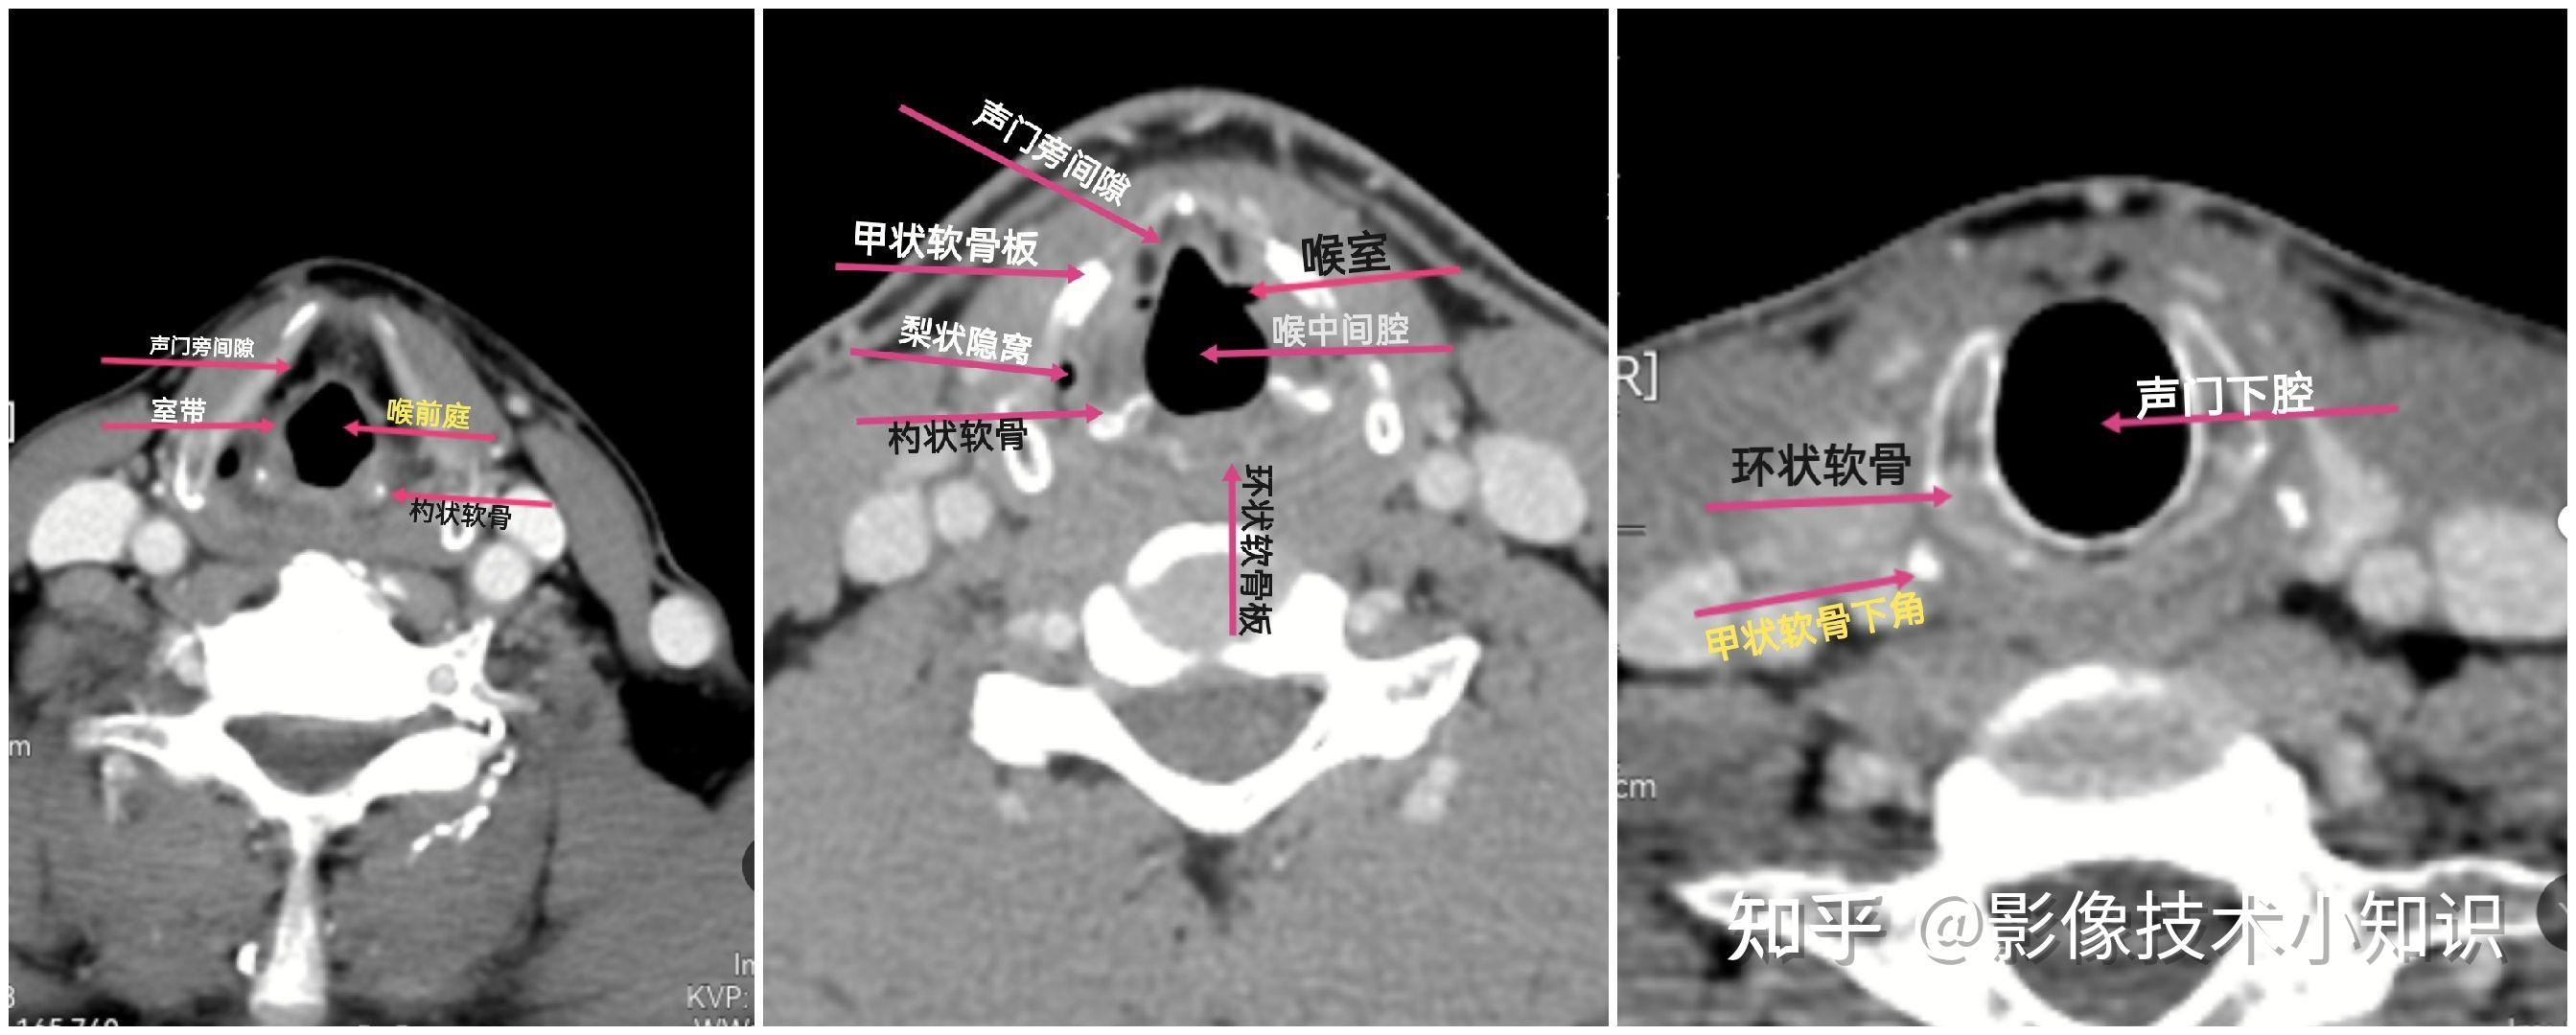

前庭襞层面即杓状软骨上突平面,见完整的甲状软骨呈弓形围在喉的前方

声襞层面在 ct 图像上,声襞和声门裂通常位于杓状软骨和环状软骨共同

(图) 经甲状软骨中份的横断层